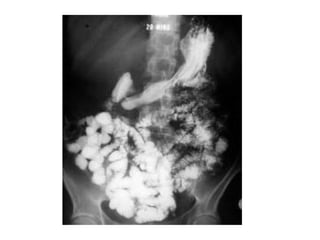

Sistema Digestório Canal alimentar : Boca, faringe, esôfago, estômago, intestinos delgado e grosso e ânus Órgãos acessórios: glândulas salivares, fígado, vesícula biliar e pâncreas

Preparar o alimento para ser absorvido pelas células (processos físicos e químicos de degradação) Eliminar escórias sólidas do organismo

Estômago Transporte Fígado, vias biliares e pâncreas Intestino Delgado Intestino Grosso Esôfago Boca Mastigação/Saliva Trituração/Reservatório/ Hidrólise de proteínas (pepsina/lipase)  Completar digestão/ absorção Adição de enzimas /suco digestivo  Absorção de água/ formação das fezes

Sistema Digestório Canalalimentar : Boca, faringe, esôfago, estômago, intestinos delgado e grosso e ânus Órgãos acessórios: glândulas salivares, fígado, vesícula biliar e pâncreas

Preparar o alimentopara ser absorvido pelas células (processos físicos e químicos de degradação) Eliminar escórias sólidas do organismo

Estômago Transporte Fígado,vias biliares e pâncreas Intestino Delgado Intestino Grosso Esôfago Boca Mastigação/Saliva Trituração/Reservatório/ Hidrólise de proteínas (pepsina/lipase) Completar digestão/ absorção Adição de enzimas /suco digestivo Absorção de água/ formação das fezes